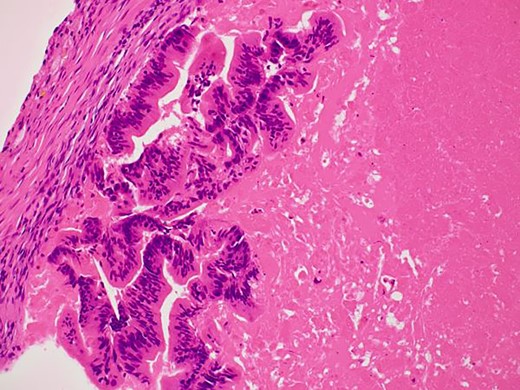

In the present case, the tumor on the patient’s abdominal wall was a lesion continuous from the deep to superficial layers of the abdominal wall. Based on immunostaining results, we diagnosed the patient with intestinal-type adenocarcinoma. Hiramatsu et al. [4] stated that when cancer and ectopic tissue coexist, identifying the transition zone between them is critical in determining the origin of the cancer. In this patient, non-neoplastic epithelial cells were present adjacent to neoplastic epithelial cells (Fig. 7a–c). These non-neoplastic epithelial cells were CDX2/CK20 positive and CK7 negative, indicating that the tumor comprised ectopic tissue of intestinal origin.

Non-neoplastic epithelial cells were present adjacent to neoplastic epithelial cells.

Differentiated ductal adenocarcinoma grew irregularly in a gourd-like pattern at the tumor area.

Non-neoplastic intestinal epithelium remained at the normal tissue area.